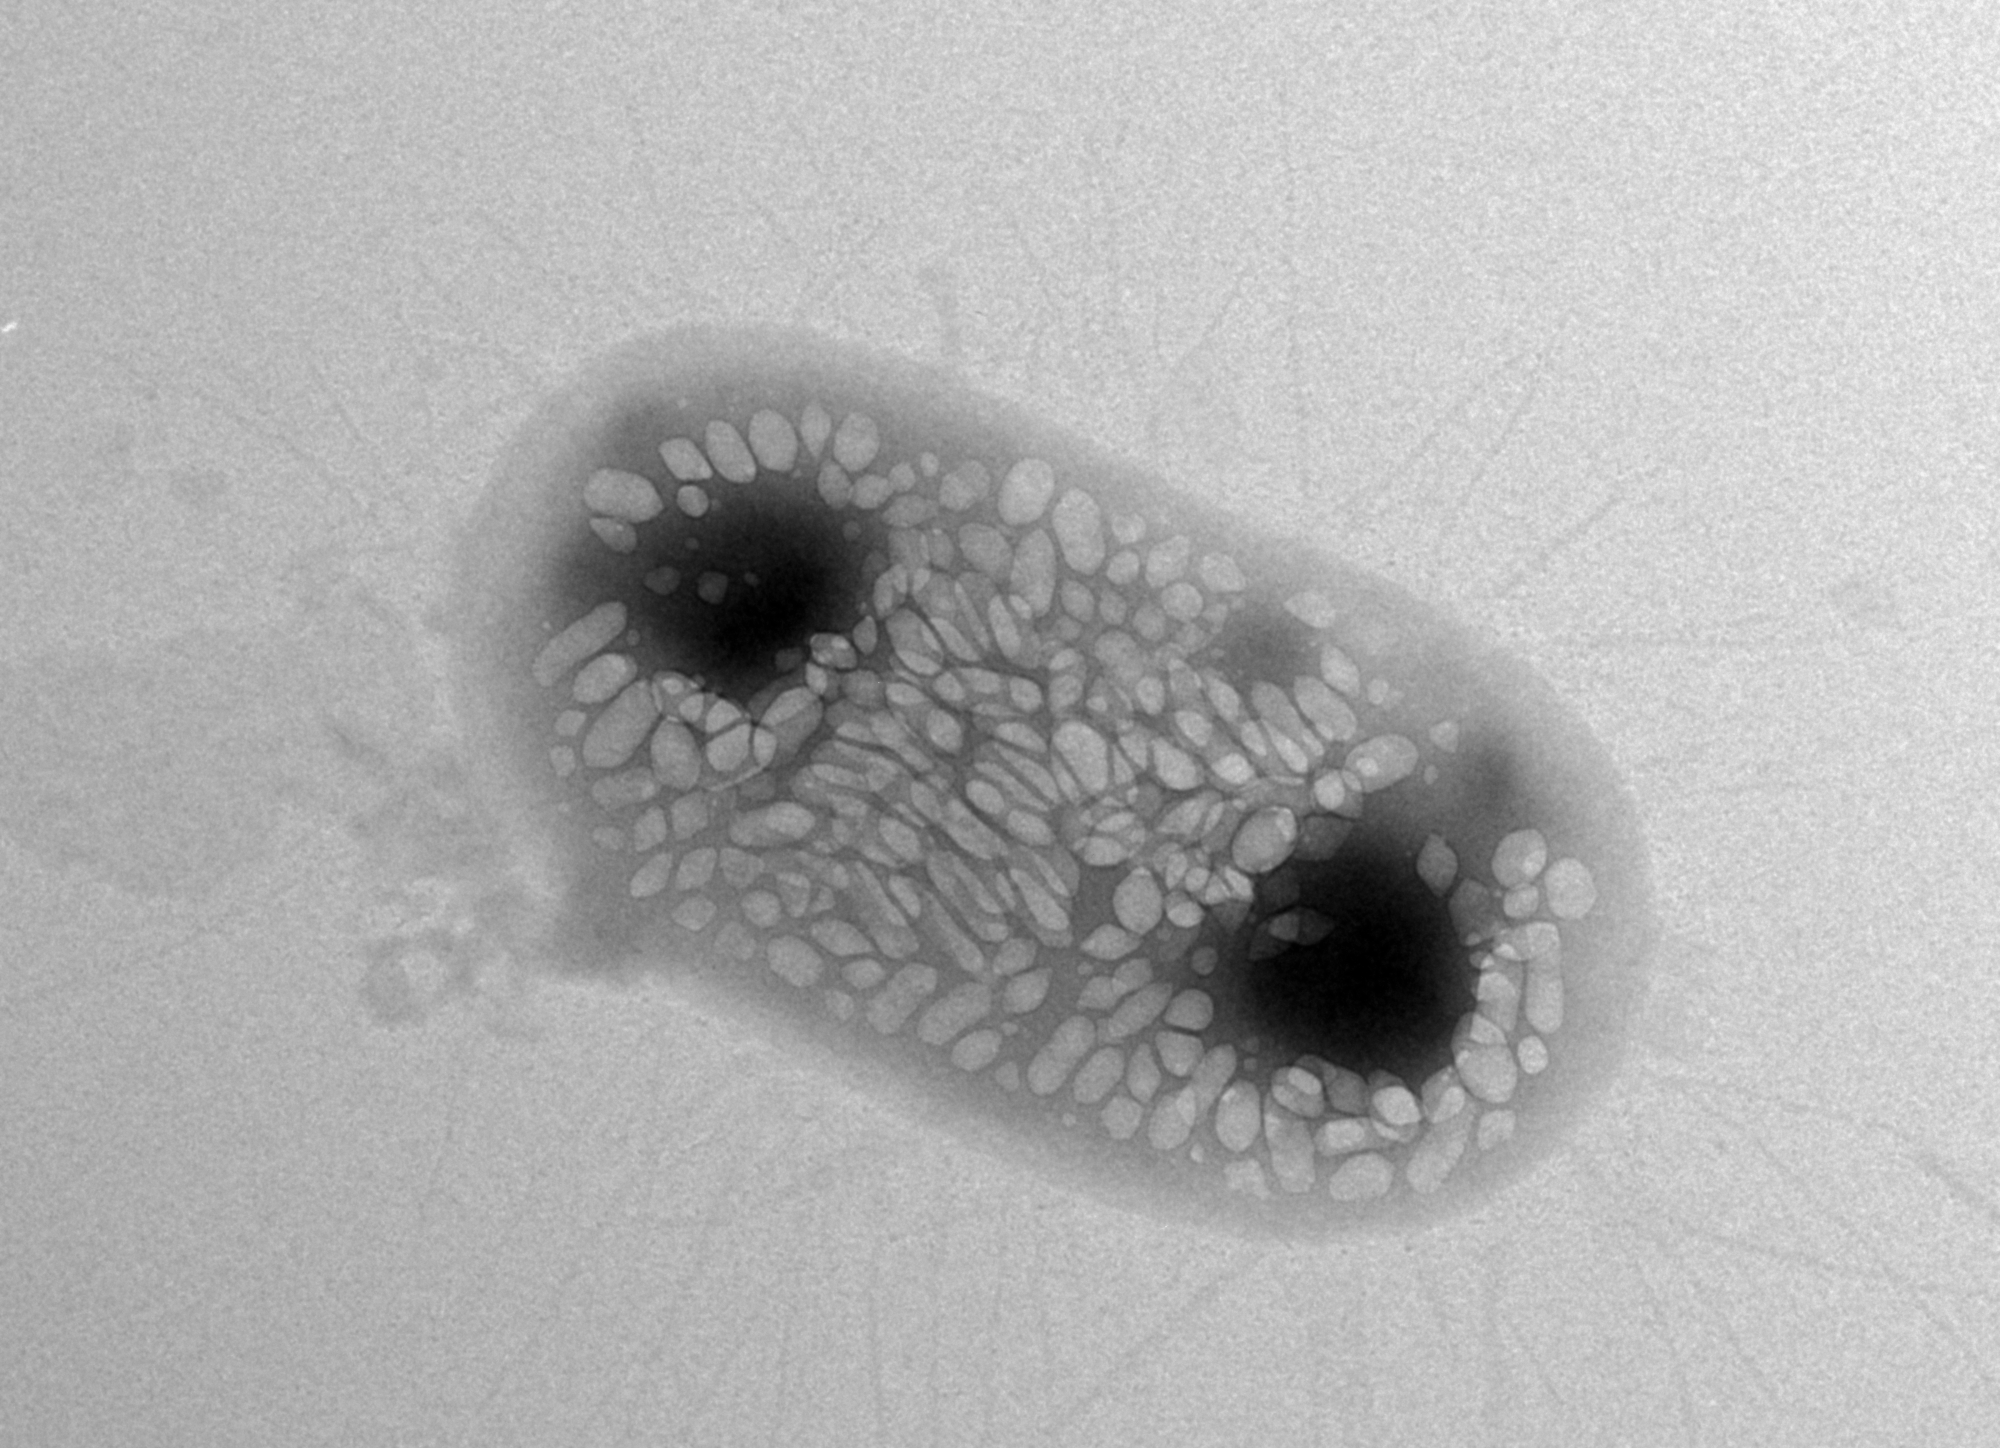

Shapiro wants to solve this problem with ultrasound techniques because sound waves can travel deeper into bodies. He says he had a eureka moment about six years ago when he learned about gas-filled protein structures in water-dwelling bacteria that help regulate the organisms' buoyancy. Shapiro hypothesized that these structures, called gas vesicles, could bounce back sound waves in ways that make them distinguishable from other types of cells. Indeed, Shapiro and his colleagues demonstrated that the gas vesicles can be imaged with ultrasound in the guts and other tissues of mice.

One of the challenges the team hit involved the transfer of the genetic machinery for gas vesicles into E. coli. They first tried to transfer gas-vesicle genes isolated from a water-dwelling bacterium called Anabaena flos-aquae, but this didn't work—the E. coli failed to make the vesicles. They tried again using gas-vesicle genes from a closer relative of E. coli, a bacterium called Bacillus megaterium. This didn't succeed either, because the resulting gas vesicles were too small to efficiently scatter sound waves. Finally, the team tried a mix of genes from both species—and it worked. The E. coli made gas vesicles on their own.

The gas vesicle genes code for proteins that act like either bricks or cranes in building the final vesicle structure—some of the proteins are the building blocks of the vesicles while some help in actually assembling the structures. "Essentially, we figured out that we need the bricks from Anabaena flos-aquae and the cranes from Bacillus megaterium in order for the E. coli to be able to make gas vesicles," says Bourdeau.

Subsequent experiments from the team demonstrated that the engineered E. coli could indeed be imaged and located within the guts of mice using ultrasound.

"This is the first acoustic reporter gene for use in ultrasound imaging," says Shapiro. "We hope it will ultimately do for ultrasound what green fluorescent protein has done for light-based imaging techniques, which is to really revolutionize the imaging of cells in ways there were not possible before."